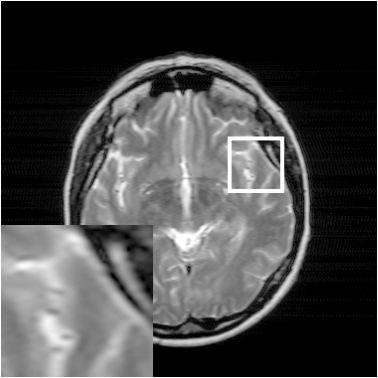

Where x is denoted as the MRI to be reconstructed, y are the k-space data, and Fusubscript𝐹𝑢{F_{u}} represents the under-sampled Fourier encoding matrix. The first term Fuxy22superscriptsubscriptnormsubscript𝐹𝑢xy22{\|{F_{u}}\emph{x}-\emph{y}\|}_{2}^{2} indicates data fidelity that can ensure the consistence between the Fourier coefficients of the reconstructed image and measured data. The second term Risubscript𝑅𝑖{R_{i}} is an analytical, sparsifying transform term, and αisubscript𝛼𝑖{\alpha_{i}} is a factor for balancing data fidelity and transform terms. MR images can be generated by inverse Fourier transform of the sampled k-space data, which are the Fourier coefficient of an object. However, aliasing artifacts (noise-like) are produced by the incoherence of under-sampled k-space in transform domain, as shown in Fig. 1.

Figure 1: The zero-filled reconstruction. (a) is a full-sampled MRI, (b) is a 20% radial sampling mask, (c) is the zero-filled reconstruction under (b), and (d) is the reconstruction using our method. Note that aliasing artifacts are clearly seen in the zero-filled reconstruction (c), which impair diagnostic information. However, our algorithm can remove these unpleasant artifacts (d).